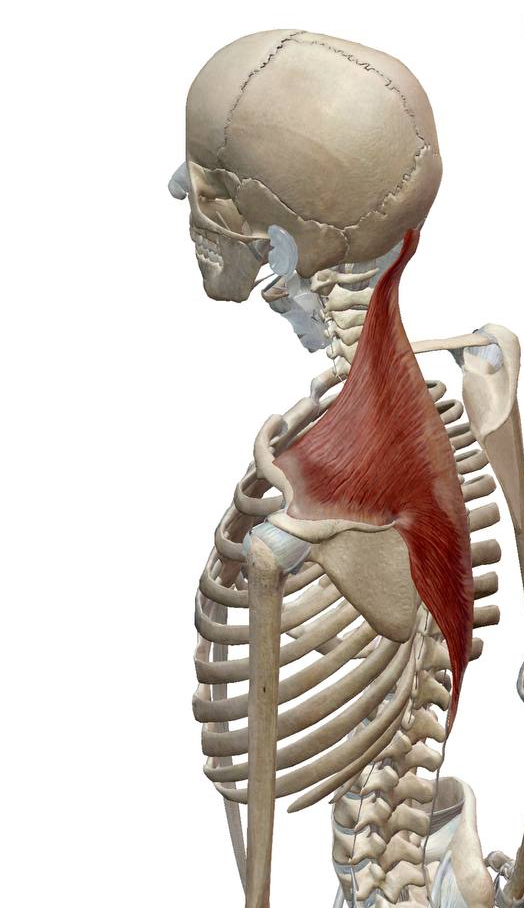

특히 승모근의만성적인 피로감과 뻐근함으로** 바로한의원에 오시는 분들이 많습니다. ## 승모근**은 뒷통수부터 목과 등을 덮는

매우 넓은 근육인데요.

11번째 뇌신경**인

부신경이 지배하기 때문에

스트레스에** 굉장히 취약합니다.

특히, 스트레스를 받거나신경을 많이 쓴 날에어깨가 뭉치는 일이 생기는 이유입니다.